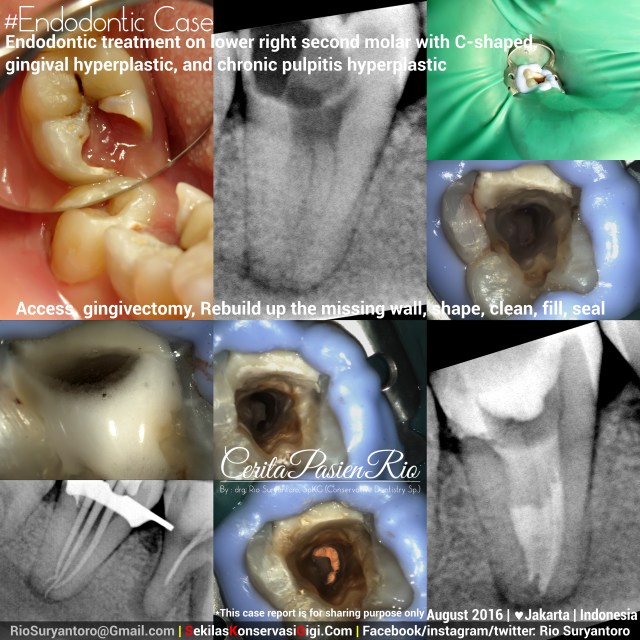

Endodontic treatment on lower right second molar with c-shaped canal, gingival hyperplastic, and chronic pulpitis hyperplastic.

This case was sent last week from my friend, also a dentist, Dr. Valeria Widita. This patient, we call it Juna, is 23 years old. Complaining about her persistent dental pain on lower molar. She had her gum bleed every time she brush her tooth

At first i saw a hyperplastic soft tissue inside tooth cavity and the gum. Tooth still vital. And the tissue origin was different between inside and outside the cavity.. after taking proper examination and informed consent, i started the dental treatment.

First, i cut the soft tissue inside and outside cavity. Waiting a while until the soft tissue stop bleeding. Then i put greatercurve matrix, and place glass ionomer cement (ketac molar – 3M) to rebuild the distal wall, prior to put rubber dam (hu friedy rubber dam clamp and blossom rubber dam sheet)

This part, i realized that i faced a c-shaped canal.

MELTON (1991) proposed the following classification based on the different configurations of the orifices in C-shaped canal systems. • Class I: a continuous C-shaped canal, with no separation of the canals. • Class II: the canal orifices resemble a semicolon (;), where a C-shaped canal is present buccally or lingually, separated from another distinct canal by a dentine wall. • Class III: two or more separate canals are present, as in a typical lower molar, with three canal orifices.

In all three classes, the “main” canals can be cleaned and shaped normally; however the instrumentation of the isthmus that connects these canals requires care, because although it may be extensive, it may also be very narrow. Copious amounts of irrigants is a must in this case..

Root canal preparation with Mtwo (VDW) with clockwise reciprocal motion. Followed with copious amount of irrigation with NaOCl 5,24%, EDTA 18% Sol (ultradent), Chx 2% (consepsis – ultradent) prior to root canal obturation.

Radiographic evaluation with VistaRay 7.1 (Durr) showed a well filled canal, intact margin of dentine-guttapercha-composite resin, and homogeneous filling.